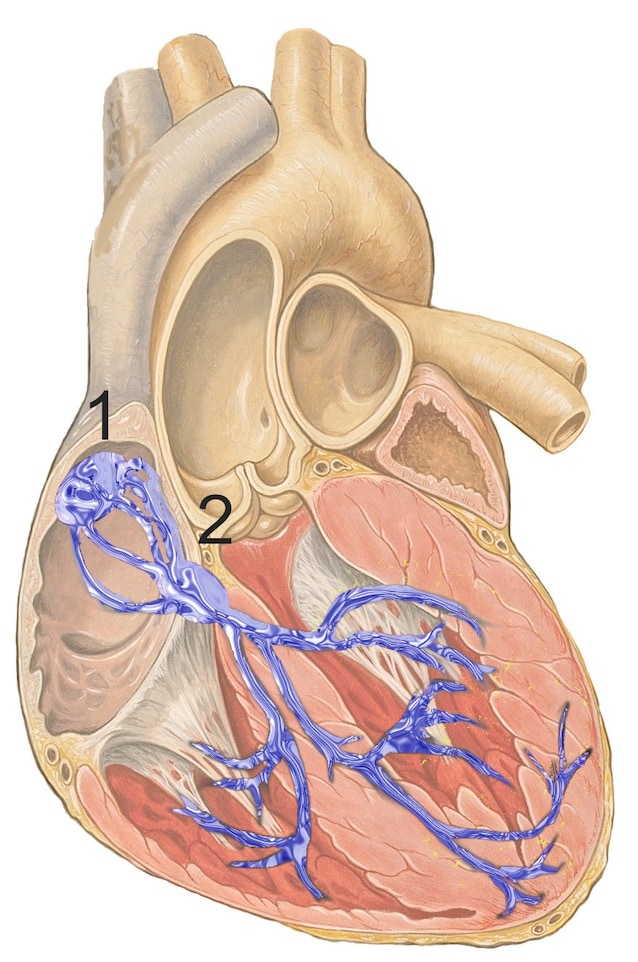

Veggene i hjertet består av milliarder av muskelceller som, hvis de er elektrisk stimulert, trekker seg sammen. En celle, etter motangrep, må fullføre frigjøringsfasen før den kan svare på en ny stimulans. Den elektriske stimulansen som får dem til å bli kontrakt med et bestemt punkt, kalt Brystknute Og det sprer seg i hjertet etter en presis vei. Riktig tidspunkt som denne impulsen når de forskjellige «kontrollpunktene» er grunnleggende for hjertets funksjon.

Det elektriske signalet starter fra brystnoden og forårsaker sammentrekning av Atri, som skyver blodet mot ventriklene. Impulsen passerer deretter til den atrio-ventrikulære noden, krysser hans bunt og er delt inn i ventrikulære grener, noe som forårsaker sammentrekning av ventriklene og utvisning av blodet fra hjertet. Denne elektriske sekvensen er grunnlaget for hjerteslaget. Men i tillegg til sekvensen, er det viktig at den elektriske stimulansen når hvert punkt med riktig timing: dette definerer hjerterytmen.

Elektrokardiogrammet (EKG) oppdager passering av den elektriske impulsen i de forskjellige punktene i hjertet. Det høyeste sporet representerer depolarisering av ventriklene, det vil si deres sammentrekning. Gjennom EKG kan leger identifisere alle Hjerteytmeavvik. Antall slag per minutt, det vil si frekvensen, kan variere, for eksempel under fysisk aktivitet, men selve takten må alltid være den samme. Ellers snakker vi om Hjertearytmi. Arytmier kan ta forskjellige former, og en av de mest alvorlige er hjerteinfarktet, eller nekrose i myokardiet forårsaket av et avbrudd i blodomløpet.